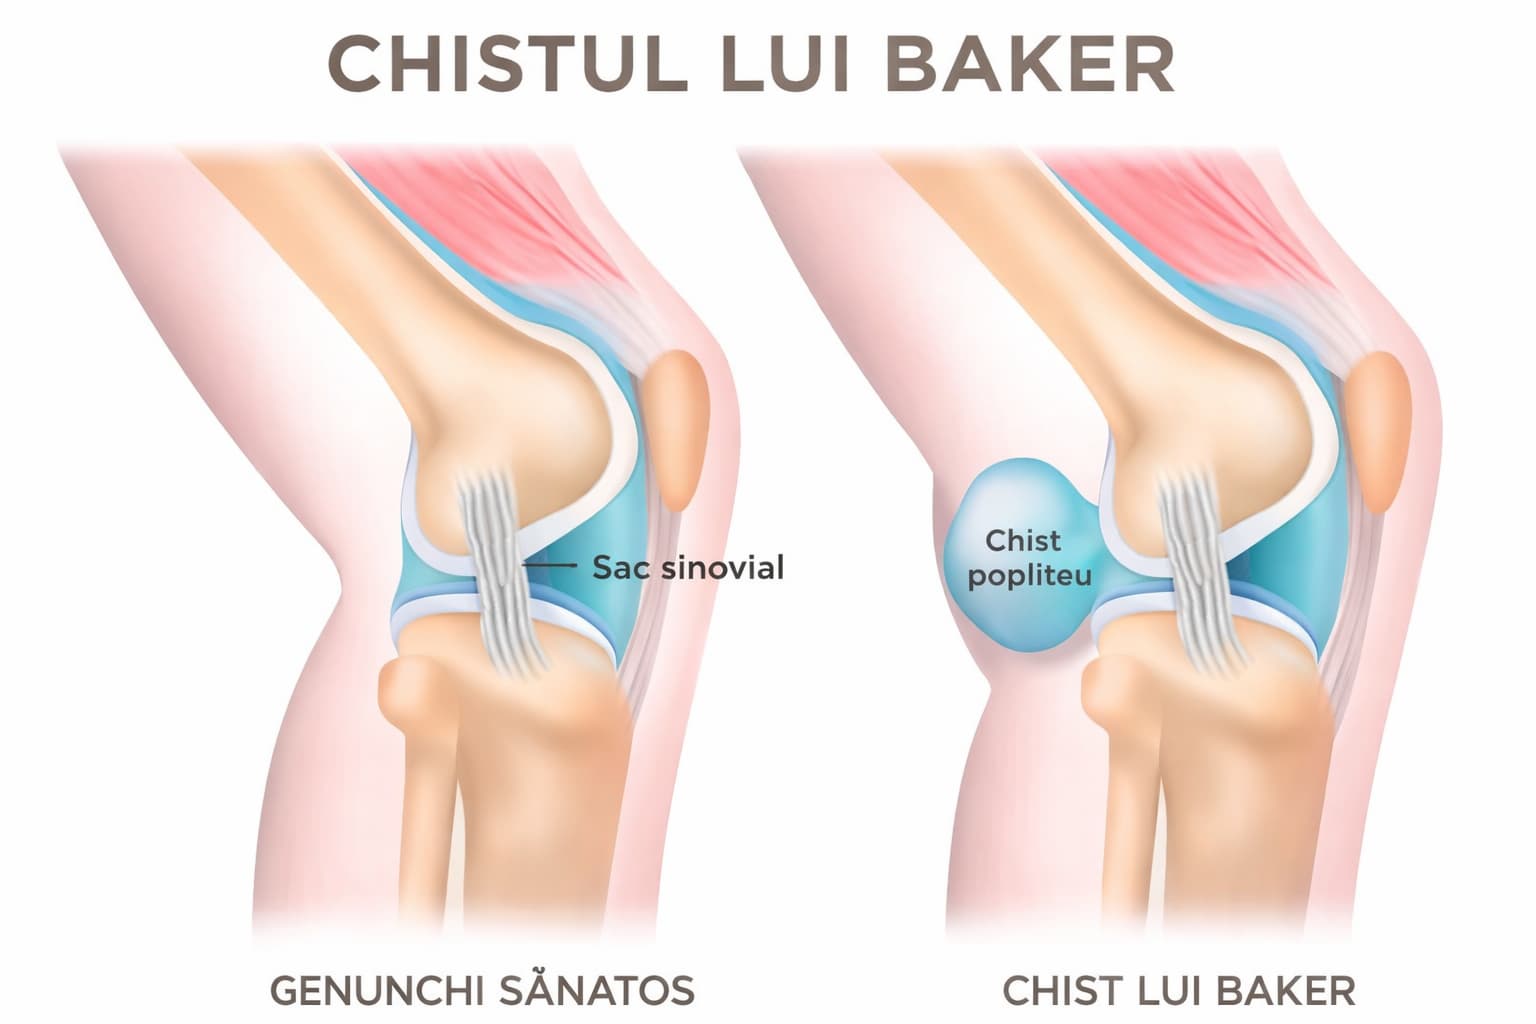

Ce este chistul Baker

Chistul Baker este o formațiune plină cu lichid situată în partea posterioară a genunchiului, în zona numită fosă poplitee.

Acesta se formează atunci când lichidul sinovial produs de articulația genunchiului se acumulează în exces și se deplasează în spatele genunchiului, unde formează o umflătură.

În general, chistul Baker apare ca urmare a unei afecțiuni care determină inflamația articulației.

📌 Atunci când articulația produce prea mult lichid sinovial, acesta se poate acumula în spatele genunchiului și poate forma chistul.

Chistul Baker este o acumulare de lichid în spatele genunchiului care apare frecvent în asociere cu alte afecțiuni ale articulației, precum gonartroza sau leziunile de menisc.